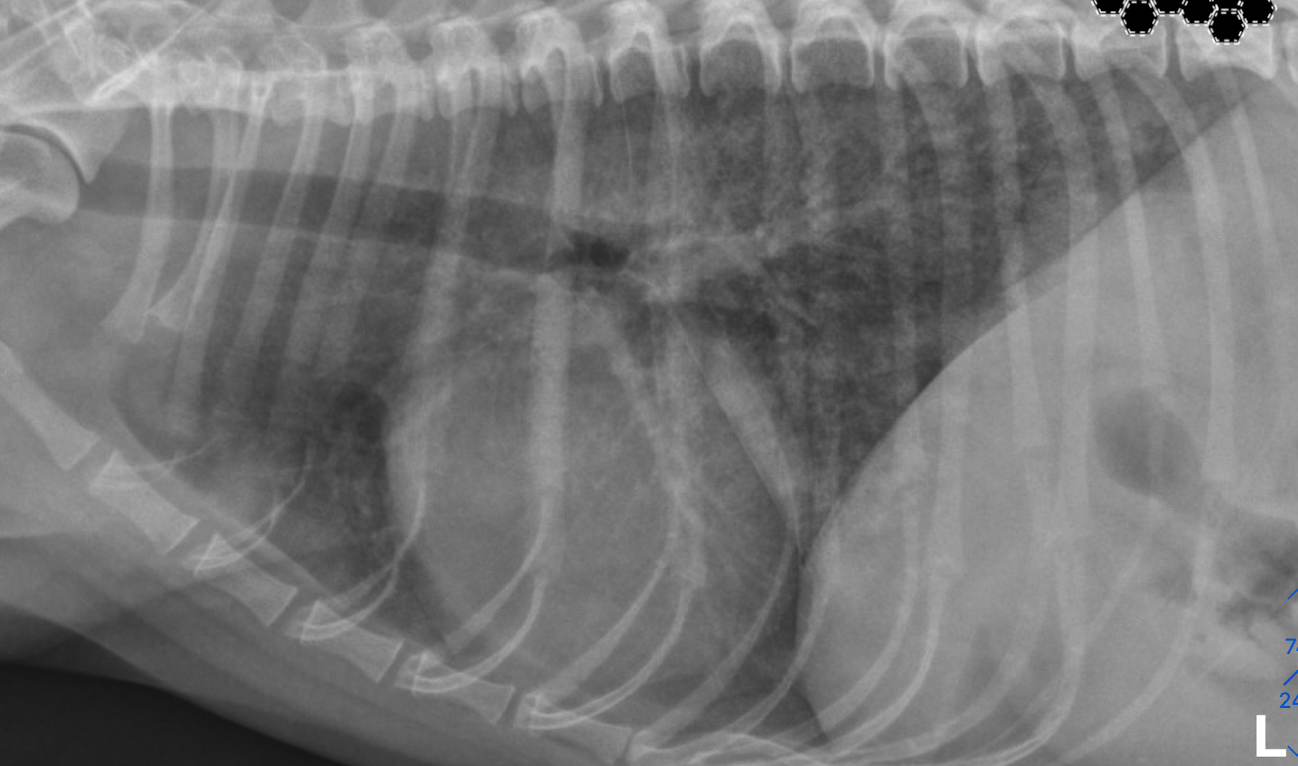

what type of pattern

right caudal lobe: intersitial- can still see vessels

left caudal lobe- alveolar- can not see vessels, can see air bronchiogram

cardiogenic pulmonary edema

left sided cardiomegaly- left auricular bulge